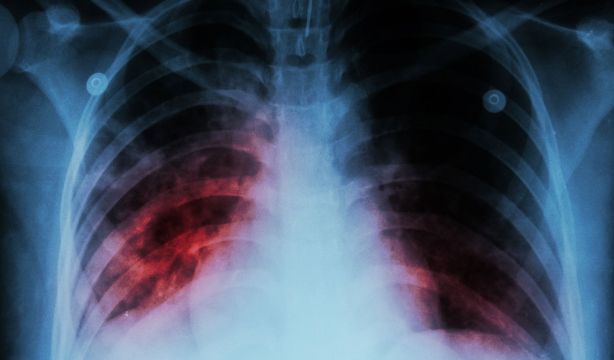

Las personas con tuberculosis tienen un 80% más de probabilidades de padecer cáncer

La Universidad Hanyang y el Hospital Ilsan de Goyang (Corea del Sur) han llevado a cabo un estudio observacional que indica que aquellas personas con tuberculosis (TB) actual o previa tienen más probabilidades de ser diagnosticadas de diversos tipos de cáncer, como el de pulmón, el de sangre, el ginecológico o el colorrectal.

A pesar de que es posible curar con éxito la tuberculosis, se pueden producir complicaciones en diversas localizaciones del cuerpo debido a la respuesta inflamatoria del huésped y los daños estructurales, vasculares, y las anomalías metabólicas que conlleva la enfermedad.

Entre estas complicaciones, un mayor riesgo de padecer cáncer.

Tras la tuberculosis puede haber una interrupción de los procesos normales de reparación génica y los factores de crecimiento presentes en la sangre.